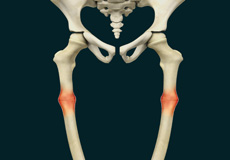

Hemihypertrophy

Hemihypertrophy also referred to as hemihyperplasia, is a rare disorder in which there is overgrowth of only one side of the body due to an excess production of cells, causing asymmetry.